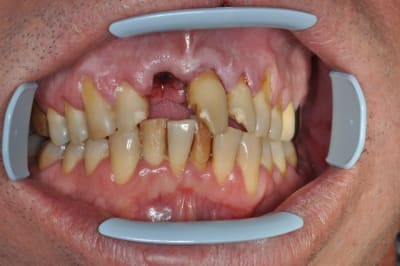

rixe routière